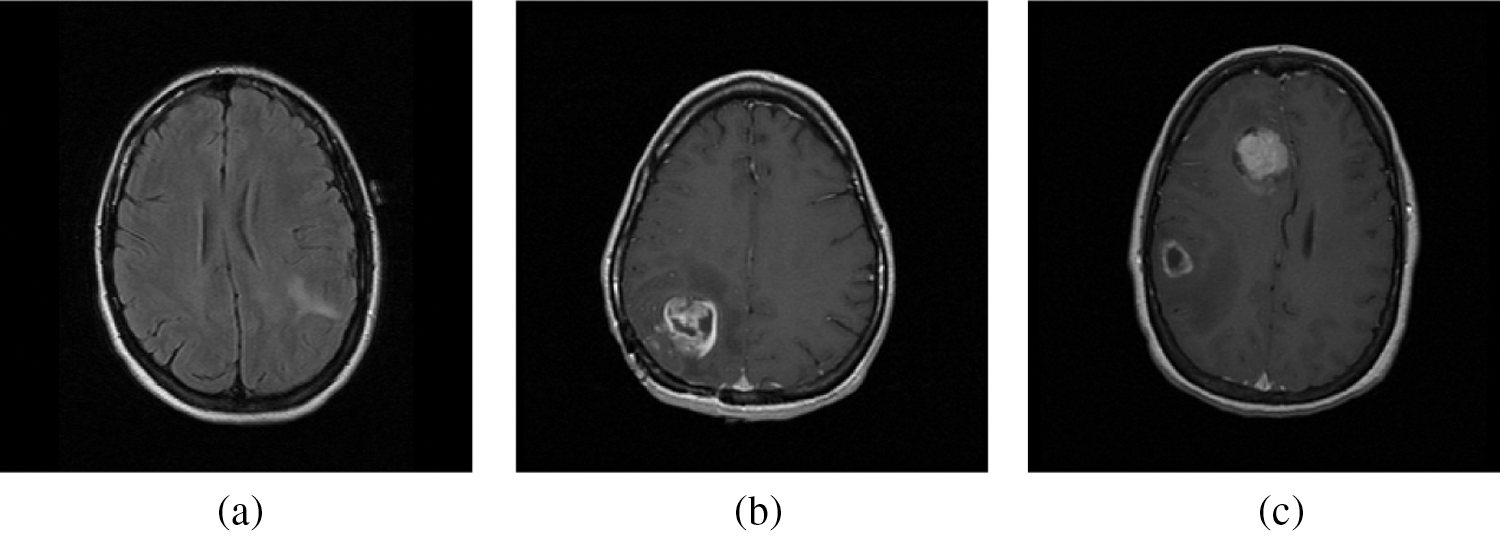

For any classification system to operate as a potential classifier, the training samples should offer an accurate representation that defined each category. In this work, the training samples are obtained from the on-line freely available database; REMBRANDT database [26–28]. At first the DICOM images of size 256 × 256 are converted into bitmap format and then used for further processing. From the database, 100 normal, 50 low-risks, 50 high–risks images are selected for analyzing the BEL system. Three samples per category from REMBRANDT database images are shown in Fig. 5. The performances of the BEL system are analyzed in two stages; initial stage (normal/abnormal prediction) and final stage (low-risk/high-risk prediction). In both stages, the following performance metrics; sensitivity (Sn), specificity (Sp), and accuracy (Ac) are computed. The computation of BEL system performances are shown in Tab. 3.

Figure 5: A sample from REMBRANDT database images. (a) Normal MRI images (b) Low-risk MRI images (c) High-risk MRI images